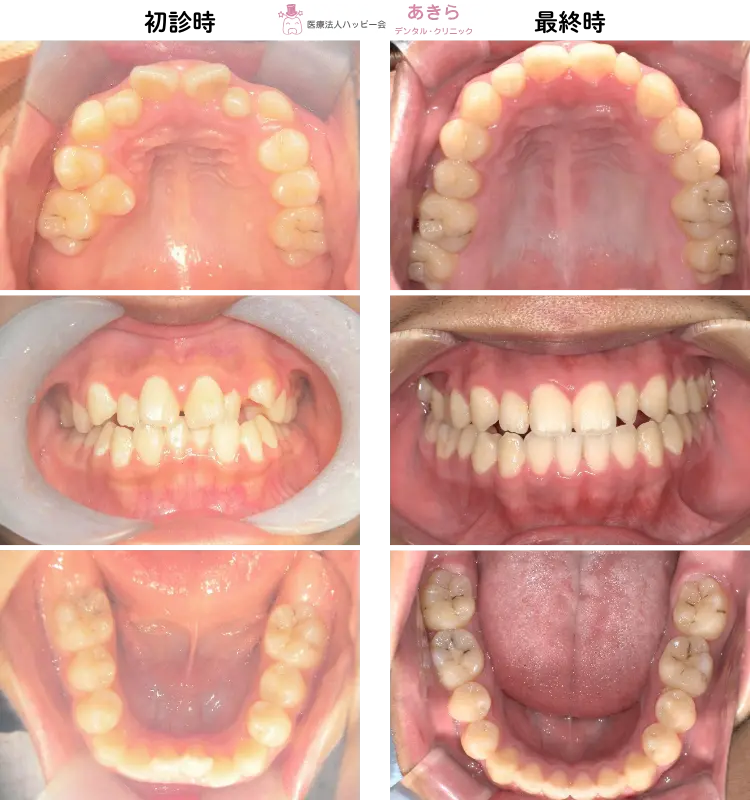

当院の症例

SH療法

SH療法-症例-No.014-左上5番の口蓋側転移位を伴なう症例

山形市の歯医者「あきらデンタル・クリニック」のSH療法の症例をご紹介します。 SH… -

SH療法-症例-No.013-右上5番の著しい口蓋側転移位を伴なう症例

SH療法-症例-No.012-外傷歯を伴う叢生(凸凹)の矯正症例

症例

予防的矯正治療(プレオルソやマウスピース型装置を主に使用)-症例-No.008

山形市の歯医者「あきらデンタル・クリニック」の予防的矯正治療(プレオルソやマ… -

SH療法-症例-No.011-下顎右側偏位を伴う「プレオルソ」を保定として使用した症例

予防的矯正治療(プレオルソやマウスピース型装置を主に使用)-症例-No.007

山形市の歯医者「あきらデンタル・クリニック」の予防的矯正治療(プレオルソやマ…